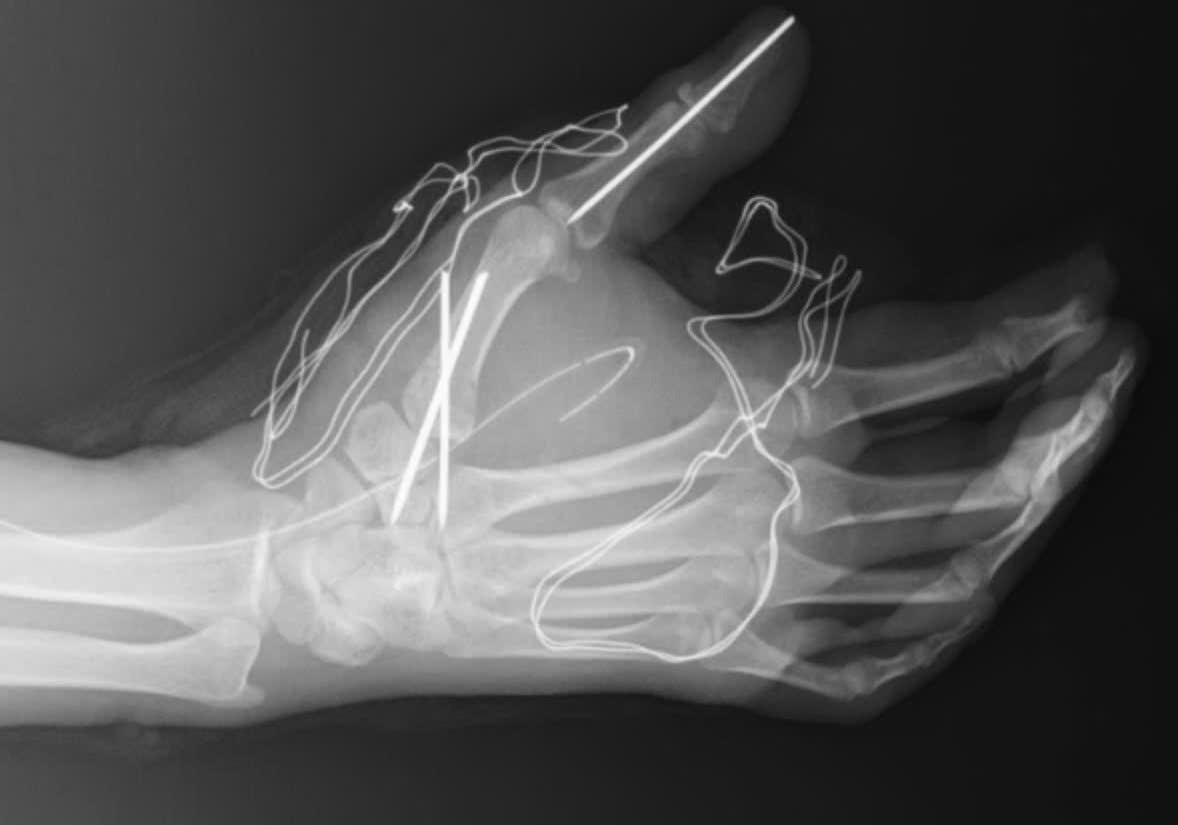

Al recibirlo, los médicos registraron que la mano izquierda del paciente estaba complejamente magullada y sangraba mucho. La herida corría el riesgo de dañar los tendones, los vasos sanguíneos y los nervios, y dentro había muchos cuerpos extraños y tejido necrótico. Si no se trataba a tiempo, el paciente podría perder la función de la mano.

Durante la cirugía, los médicos realizaron la extirpación de los tejidos magullados, extirparon el cuerpo extraño de la mano, limpiaron la herida e intentaron preservar al máximo los tendones, nervios y vasos sanguíneos restantes.

Los médicos dicen que los petardos pueden causar muchas formas de daño grave, como aplastamiento de tejidos blandos, fracturas complejas de huesos, incluso pérdida de dedos o pérdida de manos. Las quemaduras causadas por los petardos también pueden dejar graves secuelas, afectando a largo plazo la función motora.